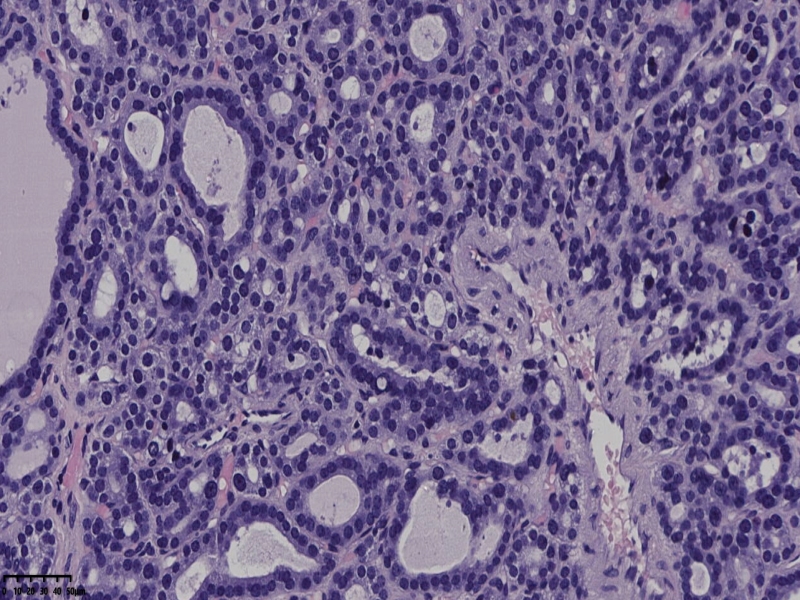

男、69、甲状腺左叶肿物,部分为囊性,囊内可见乳头状结构,上皮核重叠,没有核沟,没有毛玻璃样改变,没有核内假包涵体。255427

部分区域瘤组织与周围甲状腺组织分界明显,没有包膜样结构,滤泡结构为主,细胞异型明显。

会诊结果:(左叶甲状腺近峡部)甲状腺肿瘤,考虑为具有RAS核的乳头状癌,建议免疫组化及基因检测。